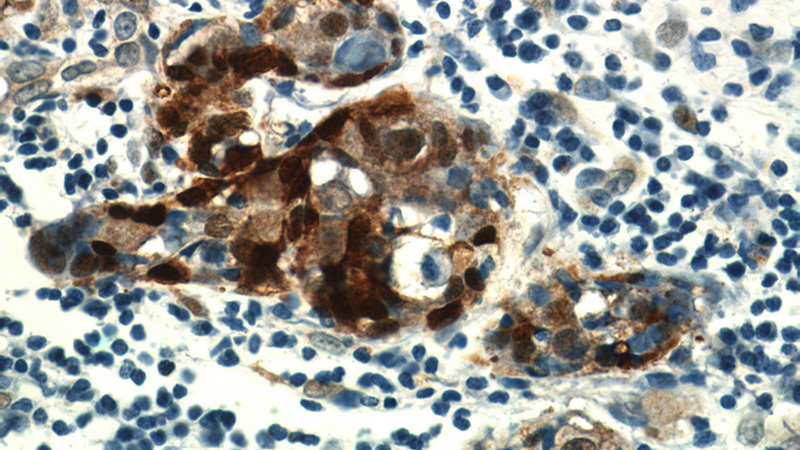

Immunohistochemical of paraffin-embedded human breast cancer using Catalog No:108861(CARM1 antibody) at dilution of 1:50 (under 40x lens)